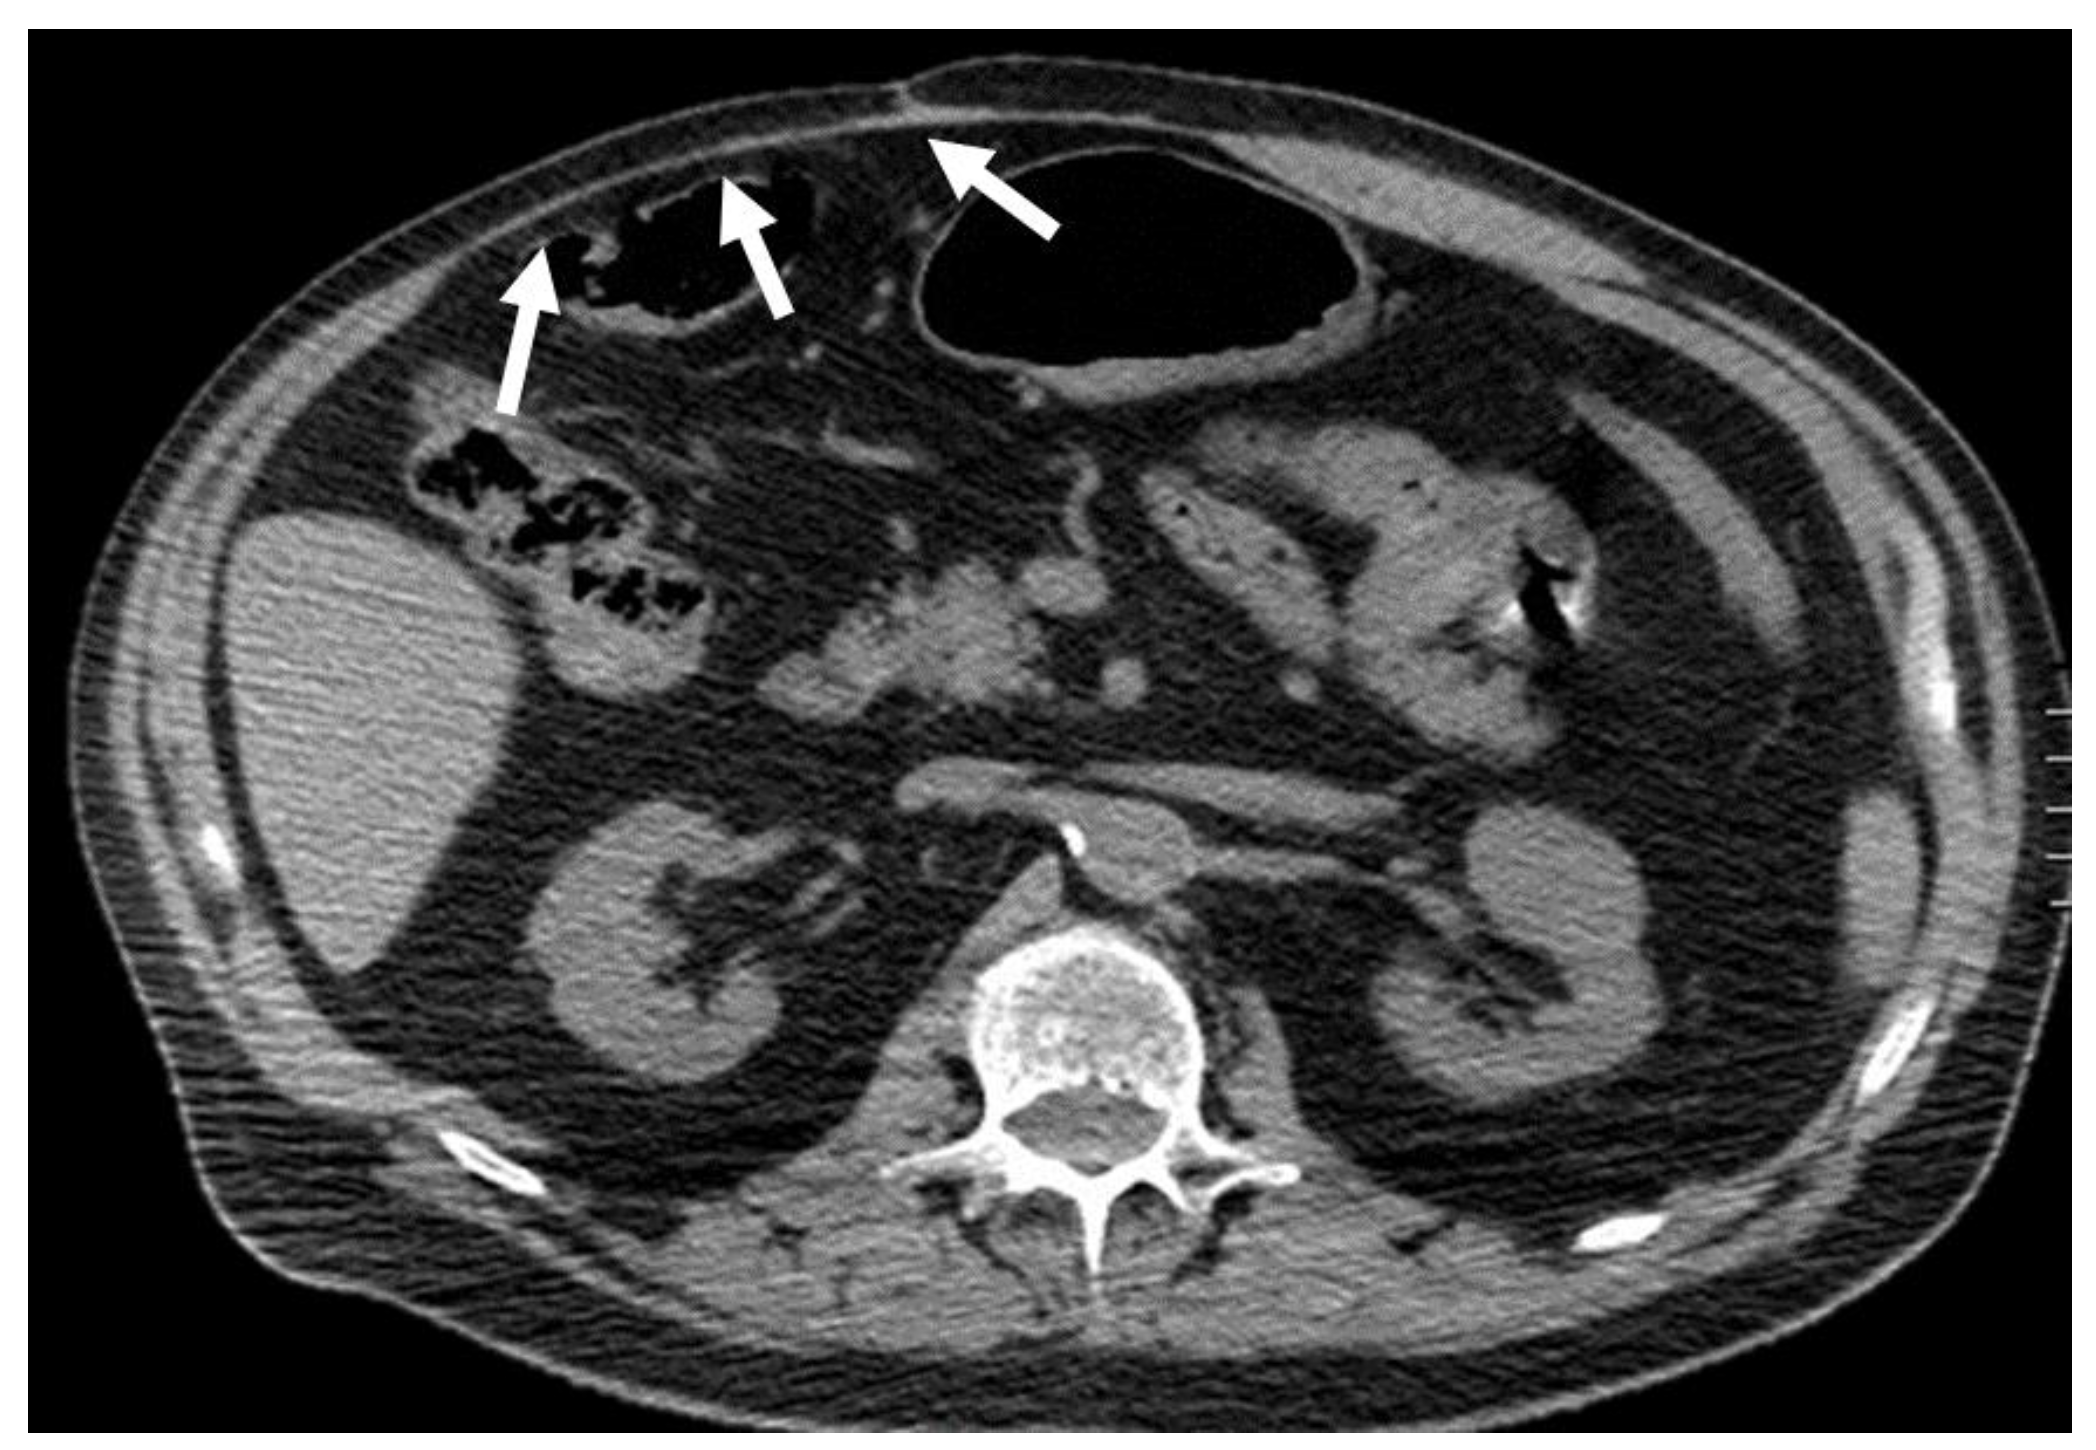

Figure 8. CT appearance of “caput medusae” on axial, contrast-enhanced CT scan on portal venous phase in two cirrhotic patients, as a result of the recanalization of the umbilical vein due to portal hypertension. This appearance is due to tortuous vessels (arrows) reaching the abdominal wall at the level of the navel.

Acquired shunts in the abdominal wall might be a sign of portal hypertension or inferior vena cava obstruction, which are both conditions to assess and not underestimate. Indeed, if untreated, the first one may lead to cirrhosis and hepatocellular carcinoma, and the latter can lead to pulmonary embolisms. Acquired shunts are caused by dilatation of the paraumbilical veins within the round ligament [26,27,28].

The paraumbilical veins will connect the superior and inferior epigastric veins in the rectus sheath with the left branch of the portal vein at the umbilicus [29], with an appearance called “caput medusae”.

CT should be preferred, in order to study all of the other signs of portal hypertension [27]. Treatment of shunts is linked to the treatment of the underlying causative condition, although in some cases bleeding can also be seen (Figure 8).